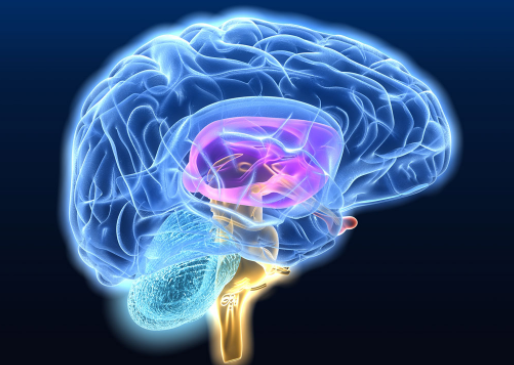

Όσοι δεν γνωρίζουν, το Αλτσχάιμερ είναι η πιο κοινή μορφή άνοιας, η απώλειας μνήμης δηλαδή. Αυτό προκαλείται από την συσσώρευση τοξικής πλάκας στους νευρώνες του εγκεφάλου, η οποία εν τέλει τα καταστρέφει. Θεωρείται ότι αυτή η ουσία, που δημιουργείται από μια πρωτεΐνη, που λέγεται αμυλοειδής βήτα, διαγράφει εντελώς τις μνήμες.

Σε έρευνα που έγινε στο πανεπιστήμιο Κολούμπια σε ποντίκια παρόμοια πάθηση έδειξε ότι, όταν διεγέρθηκαν τα σωστά νεύρα, τα ποντίκια μπόρεσαν να ανακαλέσουν τη μυρωδιά του λεμονιού που είχαν «ξεχάσει». «Τα αποτελέσματα αυτά δείχνουν ότι η μνήμη υπάρχει αλλά ότι είναι δύσκολο να ανακτηθεί ανέφερε η έρευνα που δημοσιεύτηκε στο επιστημονικό περιοδικό Hippocampus.